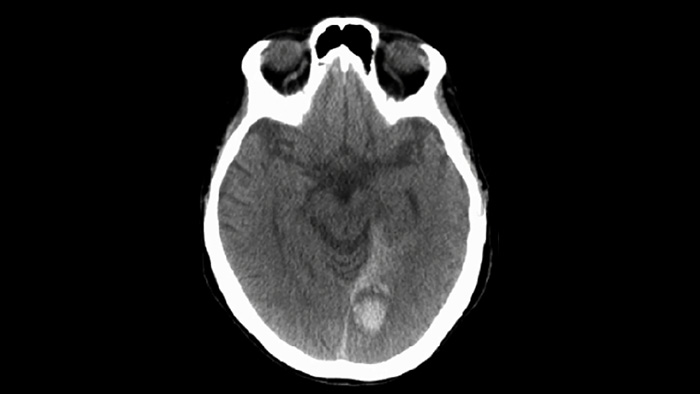

Verwenden Sie die SmartCT Soft Tissue Bildgebung der Neurovascular Suite zur Beurteilung des Behandlungserfolgs und Erkennung von Blutungen.

ClarityIQ senkt die Patientendosis von Neuro-DSA*-Verfahren bei gleichbleibender Bildqualität um 75 % gegenüber Systemen ohne ClarityIQ und ist so für eine breite Patientenpopulation geeignet. Die automatische Bewegungskompensation von ClarityIQ entfernt Schädel- und Bewegungsartefakte, was bei der Platzierung kleiner Implantate an der Schädelbasis entscheidend ist.

ClarityIQ senkt die Patientendosis von Neuro-DSA1-Verfahren bei gleichbleibender Bildqualität um 75 % gegenüber Systemen ohne ClarityIQ. Die automatische Bewegungskompensation entfernt Schädel- und Bewegungsartefakte, was bei der Platzierung kleiner Implantate an der Schädelbasis entscheidend ist.